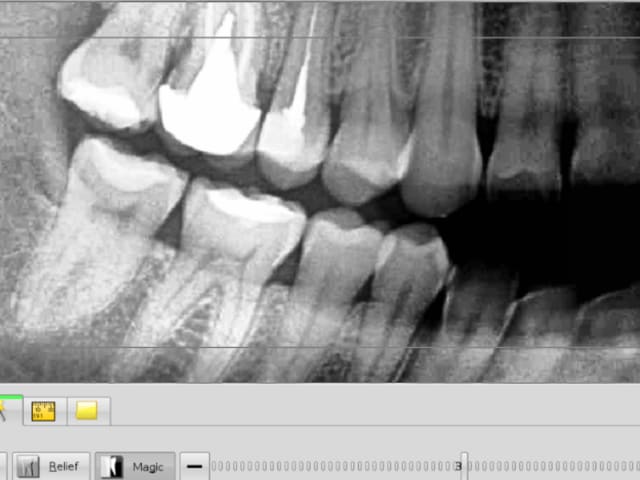

Ps : C'est un artefact radio en distal de 44 au niveau du collet?

Des clichés des apex des dents de tout ce secteur bas et haut seraient bienvenus, quant à l'angine aucun rapport, ok pour ganglion mais pas pour douleur nocturne donnant de l'insomnie", et ce au delà de la connerie de la personne.